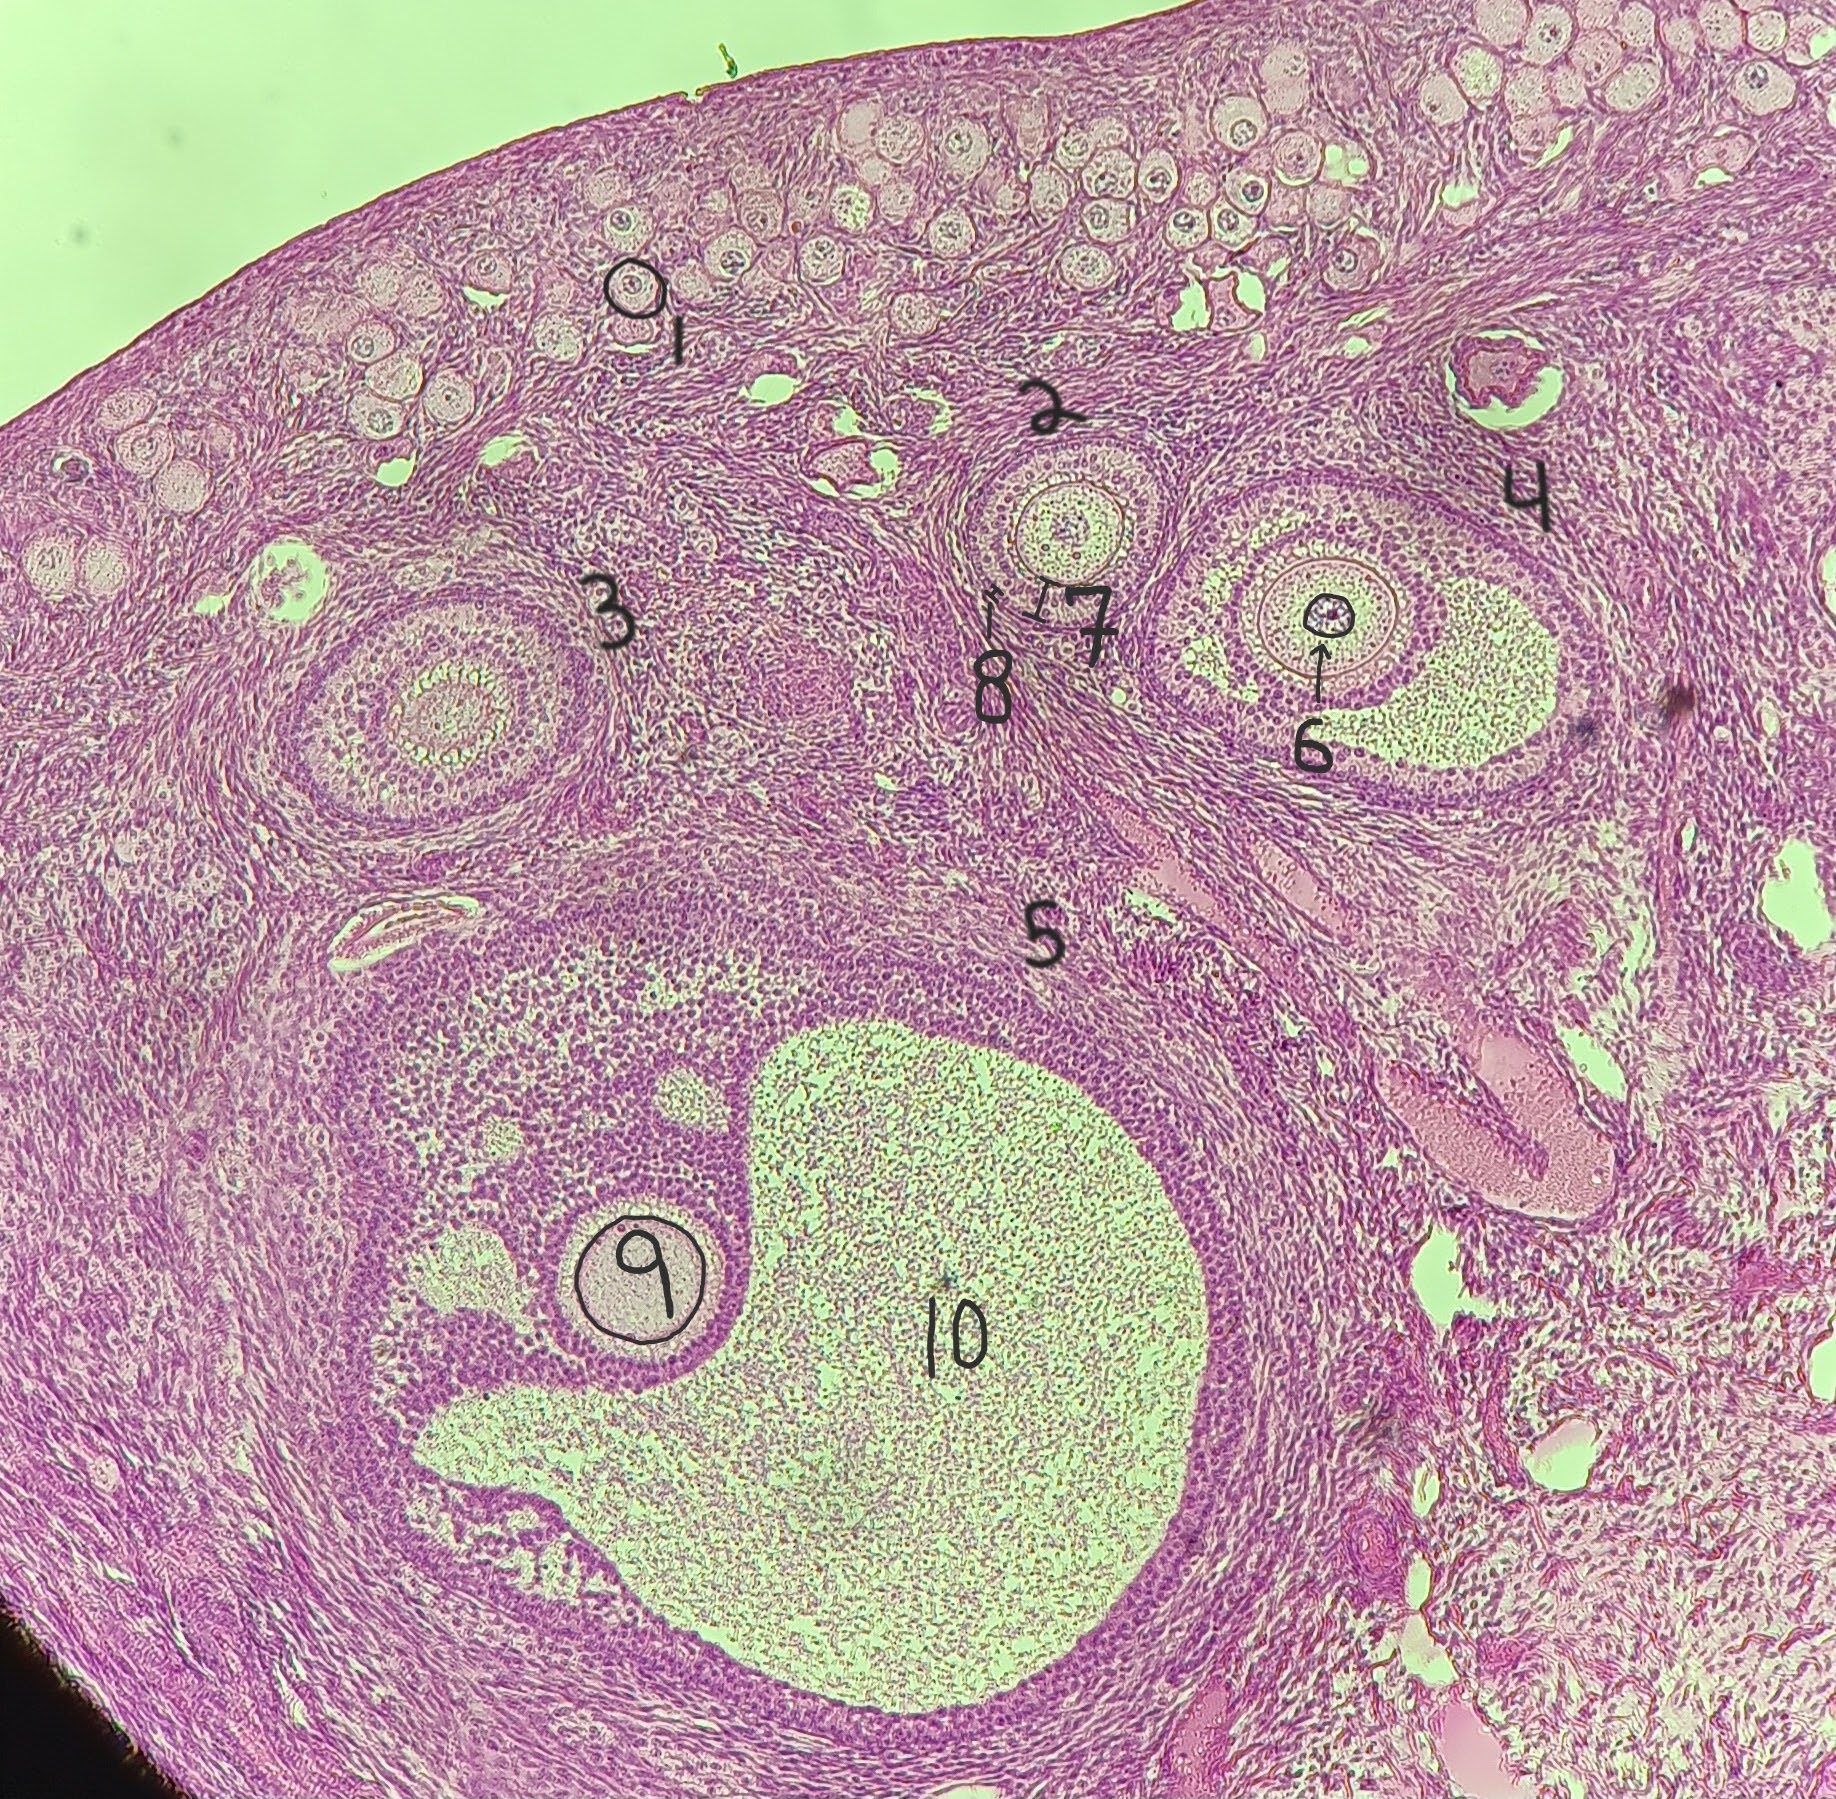

Primordial follicle

1

Primordial follicle

Primordial follicle

1

Primary follicle

2

Primary follicle

Primary follicle

2

Secondary follicle

3

Secondary follicle

Secondary follicle

3

Tertiary follicle

4

Tertiary follicle

4

Mature follicle

5

Mature follicle

Mature follicle

7

Antrum

10

Zona pellucida

9

Theca folliculi

8

Corona radiata

Corpus luteum

Corpus luteum

Corpus albicans

Corpus albicans

corpus luteum

8

early corpus luteum

9

late corpus luteum

10

corpus albicans

11